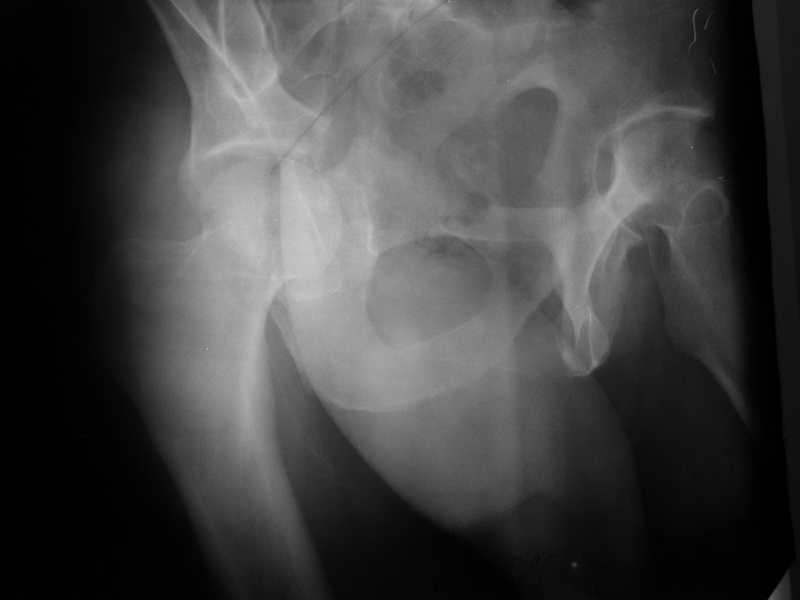

Yordan! In this case position of bone fragments is quite good. We

prefer to use miniinvasive technique. We fix posterior column by can. screw and put 3mm pin with distal thread to the anterior column. Next day after the surgery he may start walking with crutches. 3 month after the surgery we remove the pin. In cases of maleolar fractures we use

Sending exampl pict.